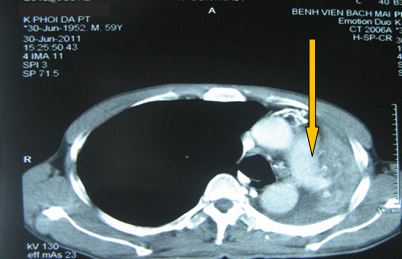

+ Chụp CT ngực đánh giá sau 5 tháng điều trị:

Sau điều trị 5 tháng

Không rõ tổn thương